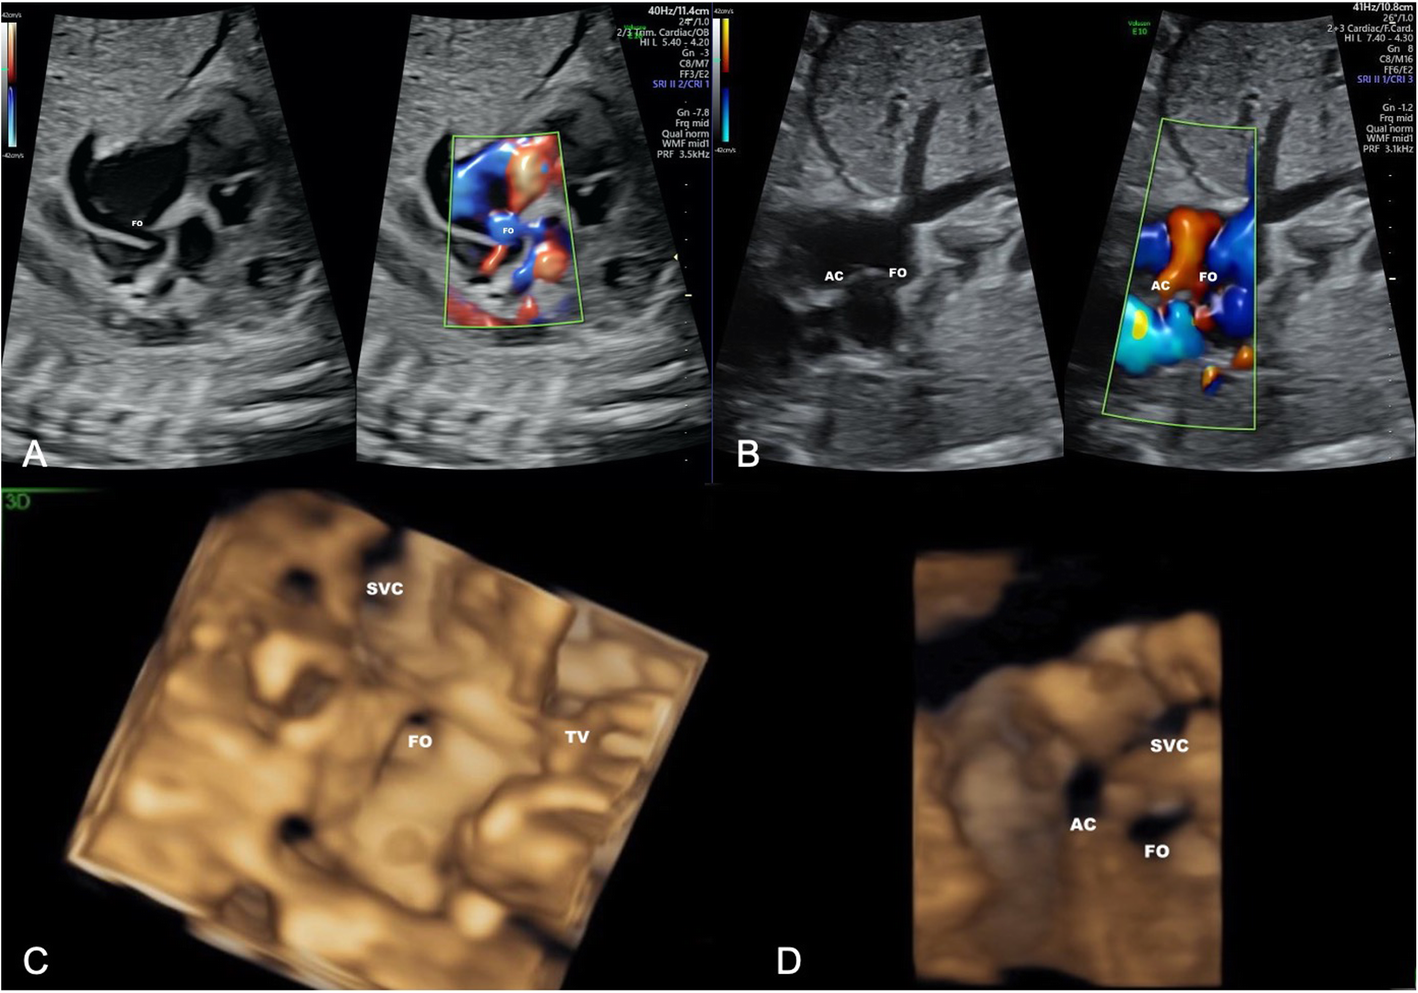

Fig. 4

Echocardiography of the fetal heart in TGA IVS and RAS before and after fetal balloon atrial septostomy (BAS). Panel A and C represents limited blood flow across the small FO prior to BAS. Panel B and D represents blood flow across the restrictive FO and additional superior atrial communication (AC) after BAS. Panel A and B were acquired using 2-D echocardiography and Panel C and D were acquired using 3-D echocardiography. TGA, transposition of the great arteries; IVS, intact ventricular septum; RAS, restricted atrial septum; FO, foramen ovale; SVC, superior vena cava; TV, tricuspid valve